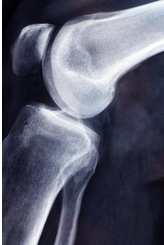

무릎 연골 손상 증상에 대해 자세히 알아보도록 하겠습니다.무릎 연골은 무릎 관절의 부드러운 조직으로, 무릎 관절을 보호하고 스트레스를 흡수하는 역할을 합니다. 연골은 대부분 물과 콜라겐 섬유로 이루어져 있으며, 신체 내부의 혈관이나 신경이 없기 때문에 손상된 경우 치료가 어려울 수 있습니다. 연령이 들면서 연골의 수명이 줄어들 수 있고, 부상이나 연골의 낭비에 따라 연골이 파손되거나 마모될 수 있습니다. 이러한 상황에서는 통증, 불안정감 및 관절 운동 제한 등의 증상이 발생할 수 있습니다. 적절한 치료를 받지 않으면 무릎 관절염과 같은 더 큰 문제가 발생할 수 있으므로, 초기에 진단하고 적절한 치료 계획을 수립하는 것이 중요합니다.

무릎 연골 정보